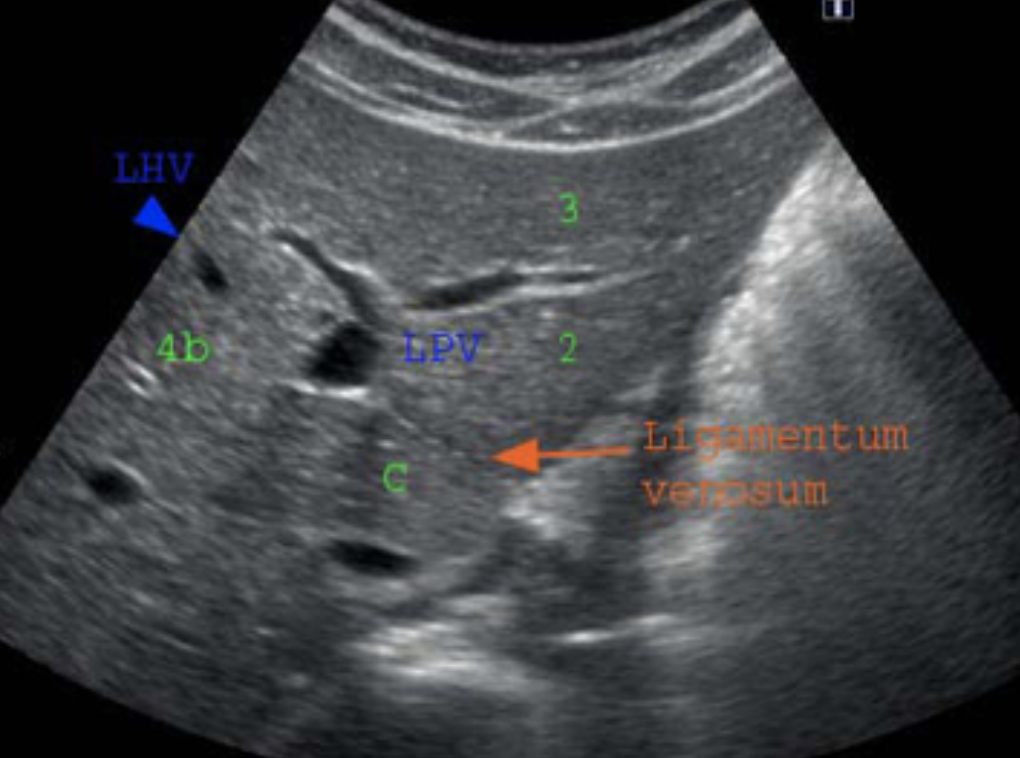

◯肝臓辺縁の評価

正常の肝臓では辺縁が鋭角で尖ってるが、慢性肝炎や肝硬変では辺縁が鈍角になって丸み帯びてくる。

(辺縁鋭の例)

http://www.ultrasoundpaedia.com/segments/